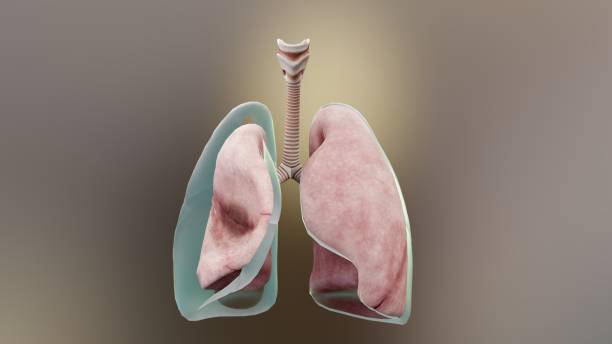

기흉(pneumothorax)은 폐와 흉부벽 사이에 공기가 쌓이는 상태를 말합니다. 이는 폐가 공기로 가득 차면서 폐가 축소되고 압축되어 발생합니다. 이러한 압축으로 인해 폐의 기능이 저하되며 호흡 곤란, 가슴 통증 등의 증상을 유발할 수 있습니다.